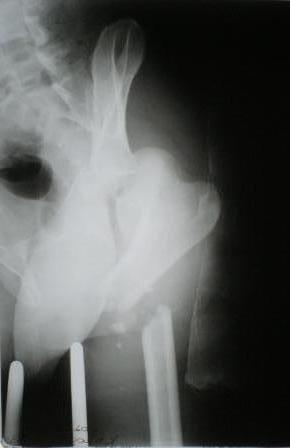

Пациент 33 лет поступил 1.02.08 с диагнозом: Множественная травма.

Т-образный перелом свода, перелом заднего края правой вертлужной

впадины. Поперечный подвертельный перелом диафиза, подвздошный вывих

правого бедра. Поперечный подвертельный перелом диафиза на фоне

консолидированного косого перелома в\3 левого бедра в порочном

положении. Открытый краевой перелом надколенника правого коленного

сустава. Открытый оскольчатый перелом н\челюсти. Закрытый неосложненный

перелом V ребра справа. В настоящее время больной компенсирован.